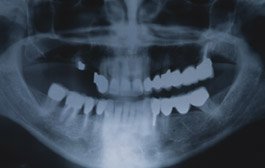

Entscheidend ist die sorgfältige Fallplanung des erfahrenen Implantologen und Chirurgen. Anhand unserer klinischen Untersuchung und Röntgenbildern klären wir die risikolose Machbarkeit der Operation ab, erklären Ihnen, wo und wie viele Implantate später möglich sein werden und erarbeiten Ihnen auf Wunsch eine Kostenschätzung. Der operative Eingriff erfolgt ambulant mittels einer normalen Lokalanästhesie (schmerzstillende Spritze), eine Narkose ist nicht nötig. Wir achten auf strikt sterile Arbeitsweise, um eine Infektion des Wundgebietes zu verhindern.

Unter einer Sinuselevation (Sinus=Schädelhöhle, Elevation=Anhebung) versteht man die operative Verkleinerung der Kieferhöhle. Die Kieferhöhle (Sinus Maxillaris) dehnt sich über den Wurzeln der Oberkieferzähne aus. Die Ausdehnung der Kieferhöhle ist individuell unterschiedlich und hängt unter anderem mit dem Zeitpunkt des Zahnverlustes in diesem Bereich zusammen. Eine weite Ausdehnung bedeutet gleichzeitig, dass für das Einbringen von Dentalimplantaten zu wenig knöcherne Substanz als Fundament vorhanden ist. Patienten, die den Wunsch haben, verloren gegangenen Zähne mittels eines fest im Oberkiefer verankerten Zahnersatzes ersetzen zu lassen und zu wenig Knochensubstanz zeigen, dürfen mit der Sinuselation diesen Wunsch realisieren lassen.